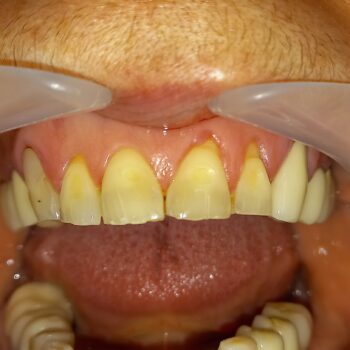

Επανάληψη απονεύρωσης σε τρία άνω πρόσθια δόντια

Διατήρηση ρίζας δοντιού με ολοκεραμικές θήκες δοντιών